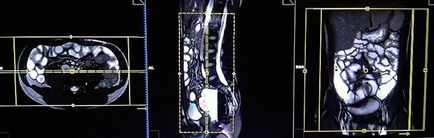

A primer szekvenciája a tervezési kell végezni képek 3 síkban TrueFISP. Ez a rövid, gyors egyetlen lövés 25 másodperc expozíciós, tökéletesen tükrözi a hasi szerveket.

Tervezés koszorúér szeletek axiális síkban; szöghelyzete a blokk keresztirányban, hogy a has, ábrán látható módon. Ellenőrizze a helyét a blokk a 2 másik síkon. Ezek között a szakaszok, hogy teljesen befedje a teljes hasüreget a hasfal elülső és a hátsó hasfal. A látómező (FOV) elegendőnek kell lennie, hogy fedezze a has és a medence a gyomor, hogy a szint a fancsonti. Annak megakadályozása érdekében műtermékek GDV kell használni fázist túlmintavételezésre (túlmintavételezés). Fontos, hogy a beteget a levegőt-hold alatt képrögzítő csomagokat. (A mi osztály, azt utasítják a pácienseket be és ki kétszer, mielőtt „be és tartsa vissza a lélegzetét” elején a scan).